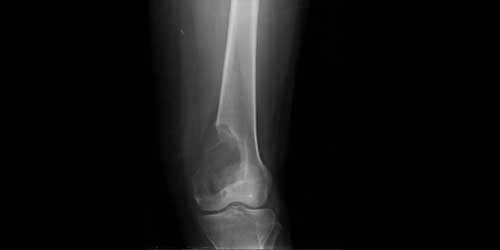

Спинальная метастаза представляет собой распространение рака на кости позвоночника, что часто вызывает боль в спине и другие симптомы. Ранняя диагностика и индивидуально подобранное лечение играют важную роль в улучшении качества жизни и эффективном контроле симптомов.